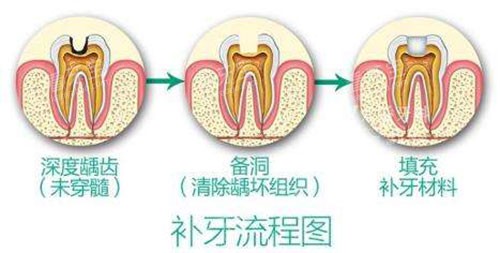

但2026年的南通口腔市场已大不同:从168元的树脂补牙到1080元的全瓷修复,价格透明得像超市价签,连材料优缺点都写得明明白白。本文结合南通较新口腔价目表和真实实例,带你拆解补牙价格的“底牌”,手把手教你避开“低价陷阱”。

南通补牙价格已形成“金字塔”结构:基础款树脂补牙168元起,中端纳米树脂300-600元,高端全瓷修复1080元起。这价格看似亲民,但“起”字背后藏着门道——比如某诊所168元的补牙可能用较普通的树脂,若想选耐磨性更好的材料,价格直接跳到368元。

避坑指南:

问清材料品牌:进口树脂(如3M Z250/Z350)比国产更耐磨,但价格高20%-50%;

警惕“低价引流”:部分诊所用168元吸引顾客,实际补牙时以“牙洞太大”为由推荐高价材料;